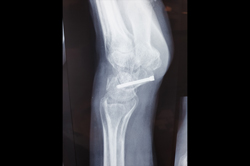

Elbow